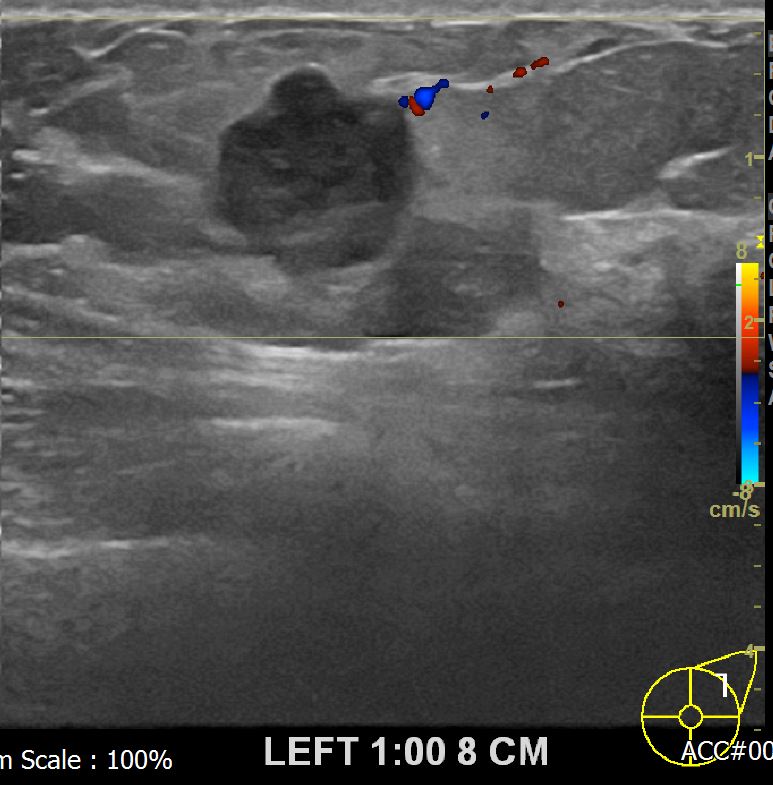

상기환자 외부검사상 이상소견으로 내원하신 50대 여성분으로  좌측유방의 의심스런혹

조직검사 시행해 유방암 진단되었읍니다.